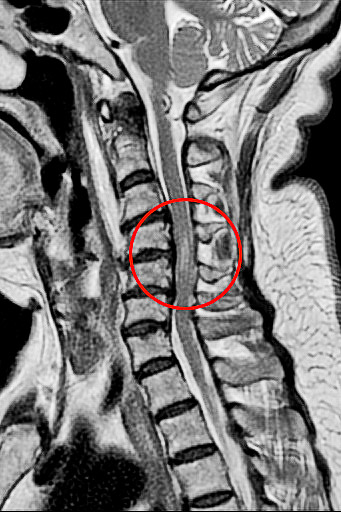

磁振造影檢查結果顯示病人頸椎第四到六節的神經被壓迫,且已造成脊髓損傷。

七十二歲的徐女士在車禍後被送往花蓮慈濟醫院急診,會診神經外科,神經外科部神經血管介入治療科主任李建輝觀察到徐女士的呼吸不太自然,只用肚子呼吸,加上手腳肌力僅剩二至三分,研判頸椎神經可能受損,進一步以磁振造影檢查確認是頸椎第四到六節之間的神經遭到骨刺壓迫,且已造成脊髓損傷。經李主任緊急以脊椎內固及融合微創手術治療,再經過中醫針灸和積極復健,徐女士於術後半個月即可下床,靠輔具行走,目前恢復良好。

李建輝主任表示,當時在急診看到徐女士,先說自己四肢癱軟無力,發現她一直在用肚子呼吸,無法自然擴胸呼吸,令他警覺有可能是頸椎神經受損,因為控制橫膈的神經就在頸椎附近,檢查後確認是第四到六節的神經被壓迫,且能清楚看到骨刺壓迫已造成脊髓損傷,有癱瘓風險,需儘快手術清除及重建,提高恢復的可能性,隨即在隔天進行手術,清除突出的椎間盤後放入填充物,並用支架固定頸椎。